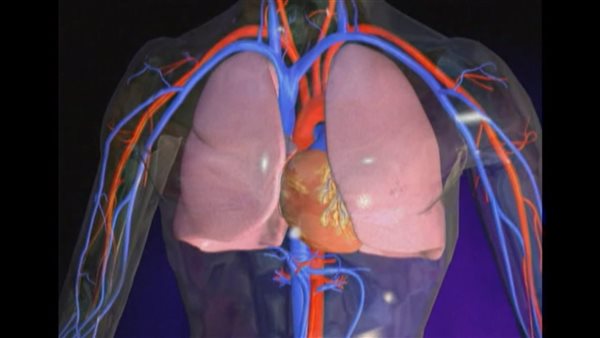

الرجفان الأذيني

الرجفان الأذيني هو اضطراب نظم القلب الأكثر شيوعًا بين البالغين، حيث يصيب أكثر من 5 ملايين شخص في الولايات المتحدة، وفقًا لجمعية القلب الأمريكية.